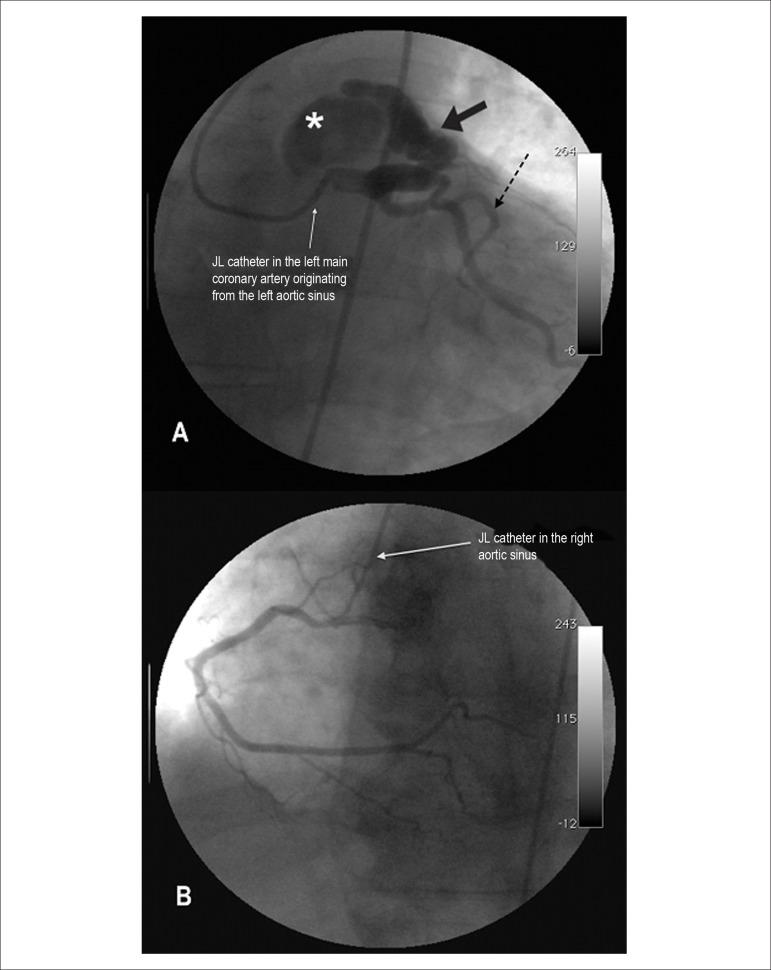

Percutaneous management of coronary artery fistula in an adult and clinical outcome.

Arq Bras Cardiol. 2013 Sep;101(3):e54-57. doi: 10.5935/abc.20130170.